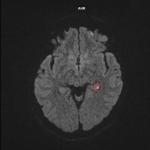

Ictus amnésique

Une femme âgée de 48 ans est vue en consultation pour un épisode d’amnésie régressive d’installation rapide (quelques...